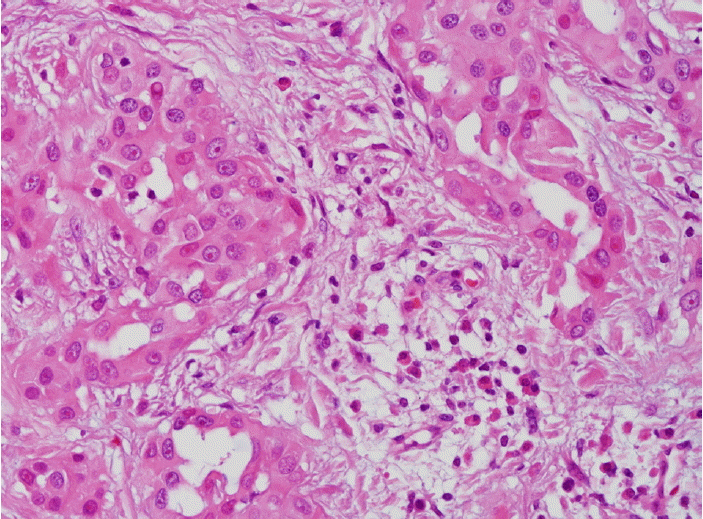

Figure 3.

Photomicrograph of specimen shows epithelial cell tumor with hyperchromatic and pleomorphic nuclei (H & E, ×400).

59세의 여자 환자가 2개월간 지속된 호흡곤란, 두근거림과 부종을 증상으로 본원 순환기내과에 내원하였다. 내원 당시 환자의 과거력상 특이소견이 없었고, 이학적 검사에서 양측 하지에 경도의 부종이 있었다. 내원 후 시행한 흉부 방사선 검사에서 경도의 심비대가 관찰되었다(그림 1). 심초음파 검사에서는 우심방과 우심실의 비대가 있었다. 흉부 전산화단층 촬영 검사에서 심막이 미만성으로 두꺼워져 있으며 불균일한 다발성 종괴가 심막을 따라서 관찰되었고, 폐 실질에는 이상소견이 보이지 않았다(그림 2). 심막에서 발생한 종괴를 의심하였고, 정확한 진단을 위해서는 조직 검사가 필요하였다. 환자는 전신마취하에 우측 개흉술을 시행하였고, 수술 소견상 심막이 미만성으로 두꺼워져 있고, 다발성 결절들이 촉지되었고, 심장과 심막과의 유착이 있었다. 우심방을 싸고 있는 심막의 결절에서 조직을 얻었고, 크기는 2×2 cm였다. 조직학적 검사 결과 상피세포 형태의 악성 중피종으로 진단되었다(그림 3). 조직검사 결과 후 시행한 양전자 전산화 단층촬영에서 심막에 미만성으로 높은 대사의 섭취(standard uptake value=6.18)가 관찰되었고, 개흉술에 의한 흉골에 국소적 대사 섭취 외에 다른 부위의 높은 대사의 섭취는 보이지 않았다(그림 4). 영상학적 검사와 조직학적 검사를 종합한 최종 진단은 심막에서 기원한 원발성 악성 중피종이다.